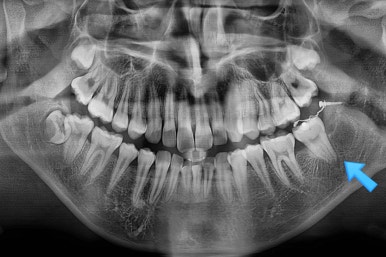

우선 사랑니는 발치하고 해당 부위로 어금니를 끌어올리기로 했어요.

환자분이 원치 않으시는 교정장치는 부착하지 않으면서 말이죠.

미니스크류를 이용하고 해당 치아에만 장치를 부착하는 부분교정을 하기로 했어요.

사랑니를 발치하며 앞쪽에 살려 써야하는 어금니에 작은 장치를 부착했어요.

어금니를 당겨줄 미니스크류도 사랑니를 발치하면서 식립해 주었어요.

해당 장치와 미니스크류 사이에 교정용 고무줄을 연결하여 지속적으로 당겨줍니다.